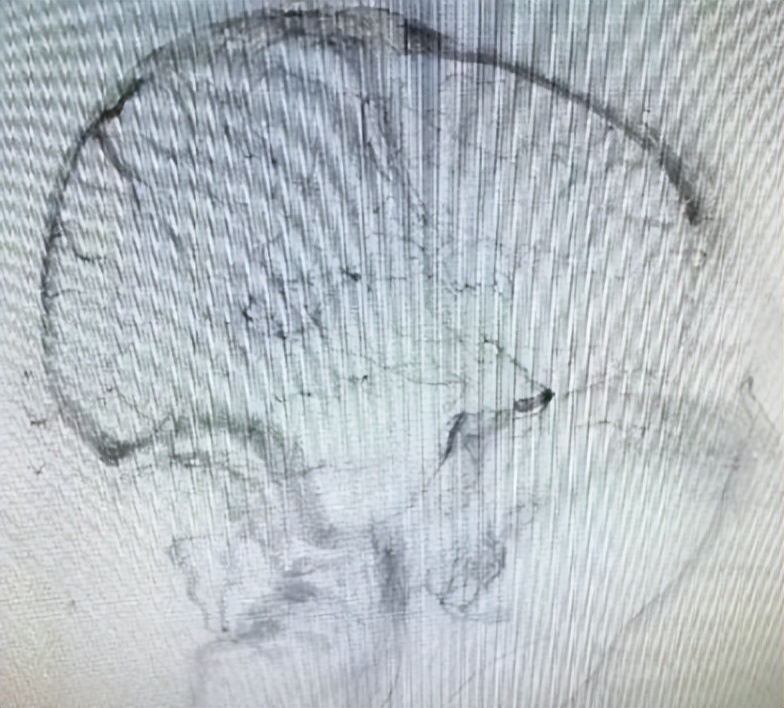

通过询问张女士家人,才知道她已经3次妊娠,都伴有血小板减少,至今血小板仍未恢复正常。急诊神经内科医生结合病情及颅脑CT的表现,第一时间做出了“颅内静脉窦血栓”的判断,同时联系磁共振静脉造影明确了诊断。然而,病魔还在牢牢地揪着她不放,3小时后她的意识障碍继续加重,并出现四肢无力,复查颅脑CT发现,她脑内的出血在不断增加。继而四肢抽搐,意识不清,生命危在旦夕。

▲上矢状窦及右侧横窦血栓